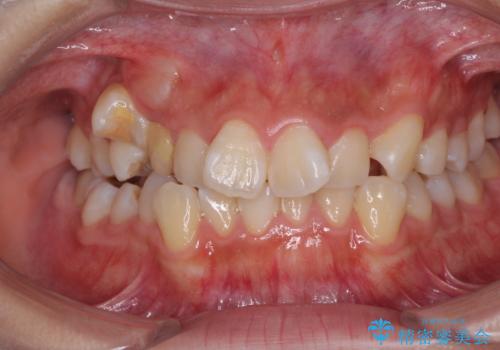

- 前歯のでこぼこと乳歯が残るほどの八重歯を気にして来院された患者様です。

非抜歯にてワイヤー矯正にて治療することとしました。(ただし、親知らずと乳歯は抜歯)

犬歯は歯根が太く長いため、移動には時間を要します。しかし、犬歯は機能面から考えて残すことを選択したいため、長期間をかけて治療を行うこととしました。